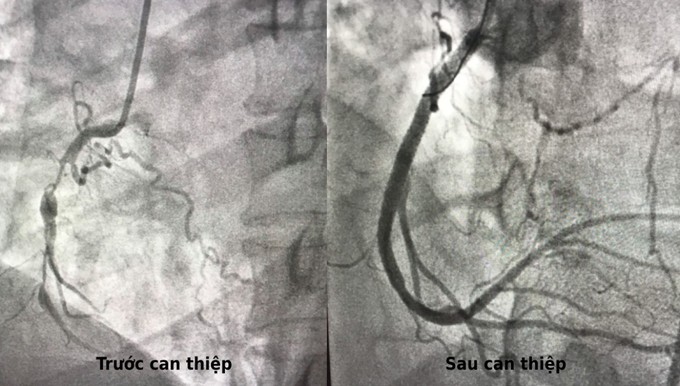

Kết quả chụp mạch vành DSA khẳng định chẩn đoán ban đầu nhồi máu cơ tim là chính xác. Ba nhánh động mạch vành tim đều hẹp rất nặng, trong đó hai nhánh lớn tắc hoàn toàn khiến máu nuôi tim không đủ, gây nhồi máu cơ tim cấp. Tìm ra nguyên nhân, ê kip can thiệp tim tiến hành đặt stent tái thông nhánh mạch vành bị tắc, phục hồi cung cấp máu vùng cơ tim nhằm hạn chế tổn thương đang tiến triển. Bệnh nhân tiếp tục được hồi sức nâng cao, thở máy kết hợp điều trị nội khoa.